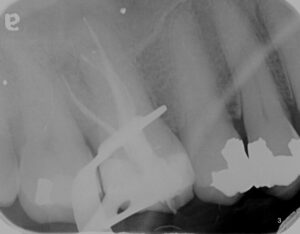

The above case shows a required a root canal treatment due to chronic apical periodontitis with sinus tract on a tooth that has a long lasting large restoration. Treatment was preformed in a single visit being able to preform the root canal treatment in-spite of calcific root canal systems under magnification using an operating microscope. As you can see in the progression throughout the x-rays the natural tooth was saved, being functional and asymptomatic.